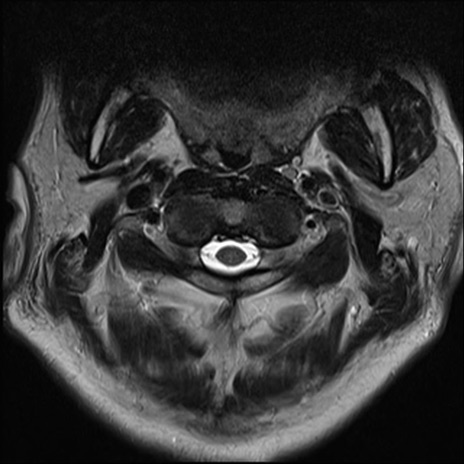

【整形】TIPS症例7 頚椎MRI T2WI(横断像)

頚椎MRI

矢状断像と横断像